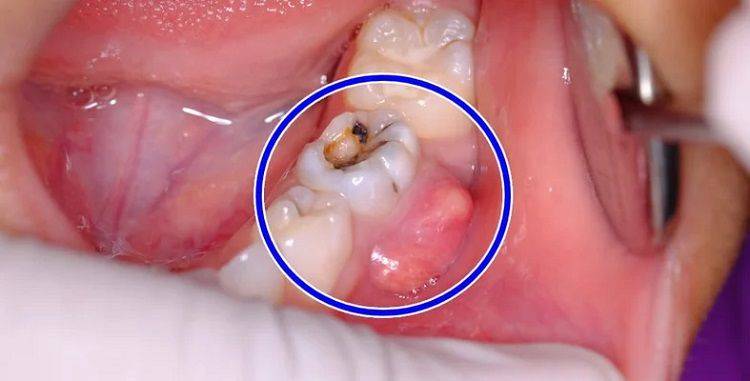

شایعترین علت ایجاد آبسه دندان پوسیدگی دندان است. وقتی پوسیدگی به عمق دندان نفوذ کرده و به پالپ میرسد، باکتریها میتوانند به راحتی وارد این ناحیه شوند و عفونت ایجاد کنند.

علاوه بر پوسیدگی، ترکها و شکستگیهای دندانی نیز میتوانند راه ورود باکتریها به پالپ دندان را فراهم کنند. در مواردی که ترک یا شکستگی دندان به پالپ برسد، عفونت به سرعت گسترش مییابد. همچنین، در صورت عدم درمان به موقع ترکها و شکستگیهای دندانی، احتمال ایجاد آبسه افزایش مییابد.